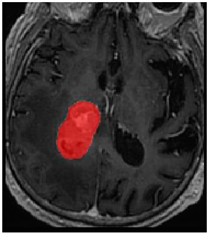

Three cases from the NTUH dataset showing representative results of different models were shown in Table 2, Table 3 and Table 4. The overall dice scores of these networks on the NTUH dataset ranged from 0.33 (DeepMedic) to 0.51 (V-Net). Table 5 shows the detailed performance of each network tested with the NTUH dataset.

Table 4. Predictions with high dice scores.

Ground truthDeconvNetDeepMedic

Applsci 11 09180 i013 Applsci 11 09180 i014 Applsci 11 09180 i015

PSPNetU-NetV-Net

Applsci 11 09180 i016 Applsci 11 09180 i017 Applsci 11 09180 i018